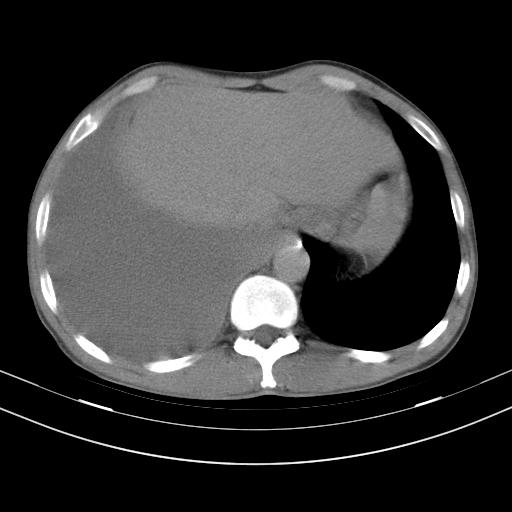

男性,44岁,结核病史多年。现胸闷气短,咳嗽,偶咳血。

右侧胸腔积液

右肺下叶不张

双肺多发结节影最分空洞形成考虑占位不除外结核

双肺陈旧性病变

1、右侧大量胸腔积液伴右肺压缩性膨胀不全,建议抽液治疗后复查 2、两肺继发性tb伴空洞形成。

1)两肺继发性肺结核伴空洞形成,左肺多发性结核球。2)右侧大量胸腔积液伴右肺部分膨胀不全。3)纵隔淋巴结肿大。

吉大一院胸水抽检结果:结核性胸水